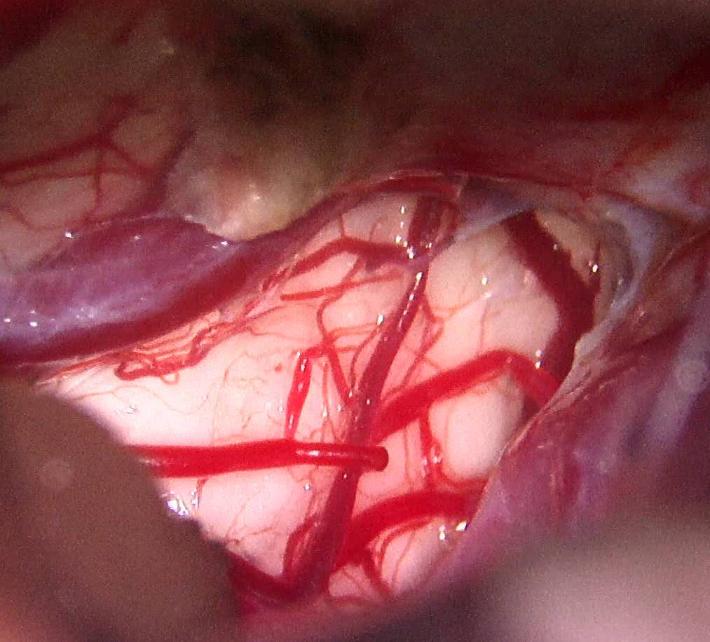

选择颞下入路,从侧方全切除肿瘤,没有选用枕下经小脑幕或幕下小脑上入路

脑干造瘘口控制在2-3毫米,全切除肿瘤并打通中脑导水管